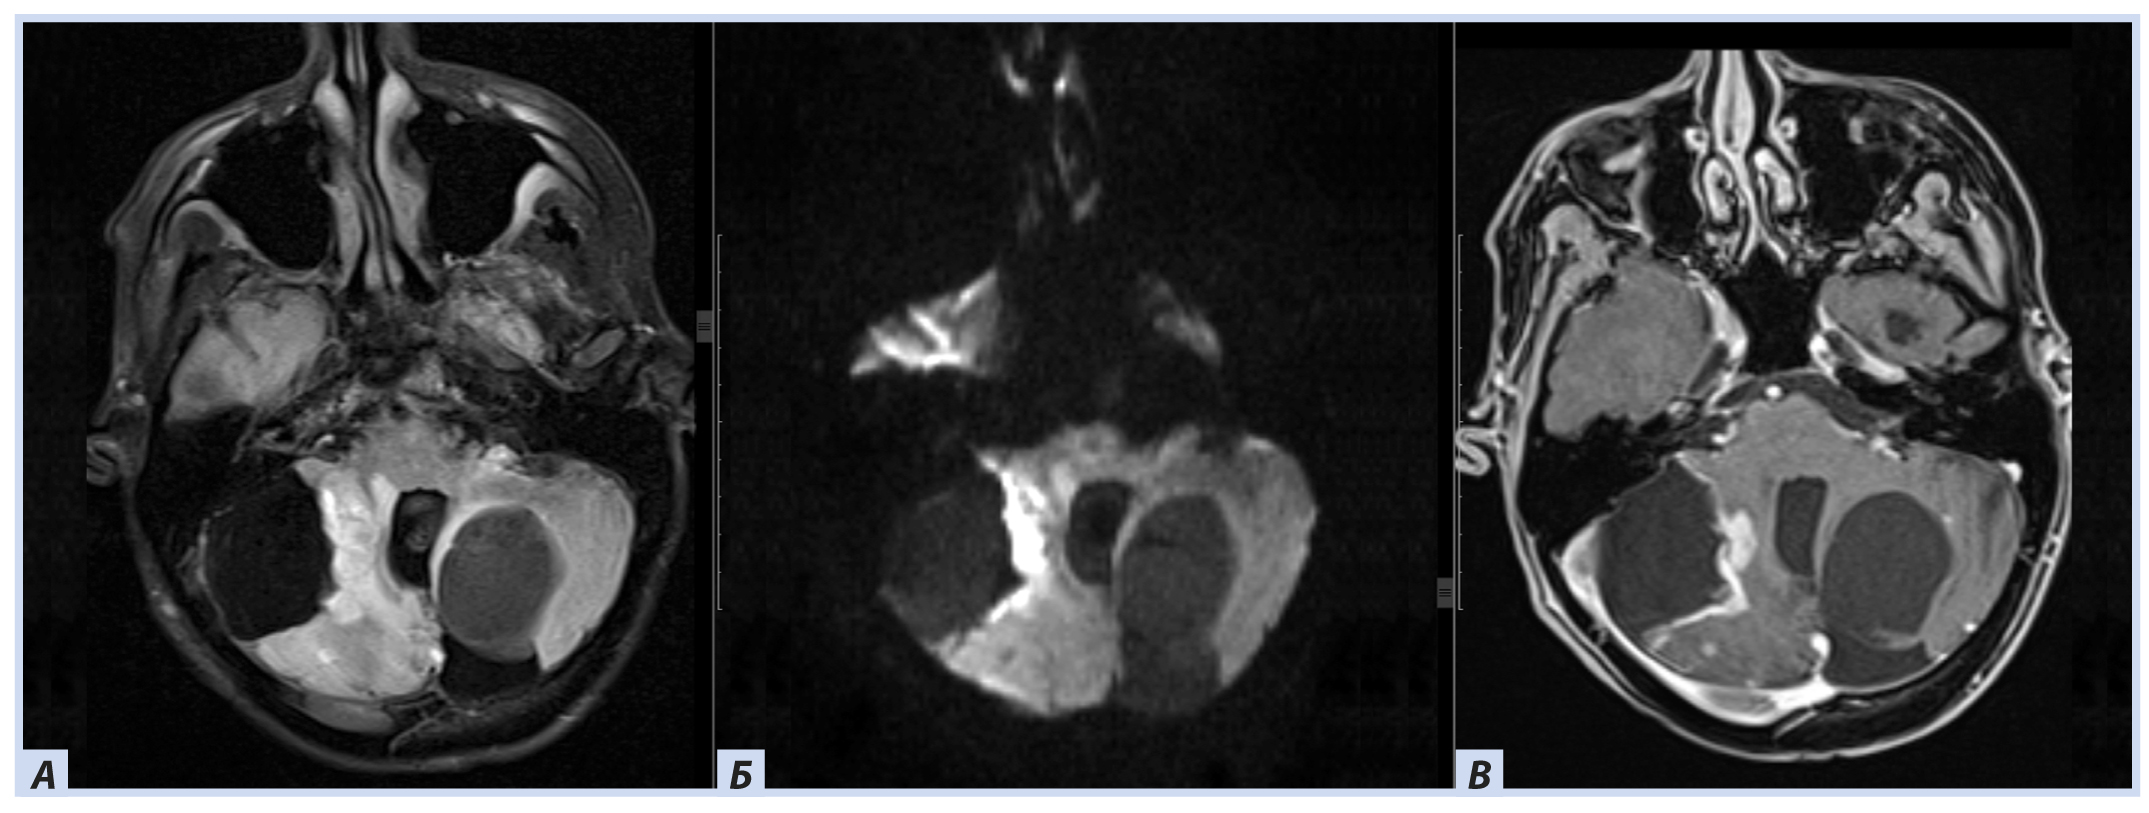

Лучевые методы. На МРТ-изображениях головного мозга выявлено характерное двустороннее поражение глаз (рис. 1), по данным КТ — с участками обызвествления (рис. 2). Также на КТ головного мозга были выявлены зона послеоперационных кистозно-глиозных изменений с наличием кисты и узла на уровне посттрепанационного дефекта в правом полушарии мозжечка, а также аналогичные зоны дорзальнее и в субкортикальных отделах; в левой гемисфере мозжечка определялись кистозные изменения (рис. 3).

Рис. 1. Пациентка П., 30 лет, с диагнозом «Болезнь Гиппеля−Линдау»: магнитно-резонансная томография головного мозга

Примечание. А, Б — Т2- и Т1-взвешенные изображения. В полости правой глазницы объемное образование с неоднородным МР-сигналом; В — постконтрастное Т1-взвешенное изображение, режим подавления сигнала от жира: определяется интенсивное, но гетерогенное контрастирование образования. Кровоизлияние в сетчатку справа.